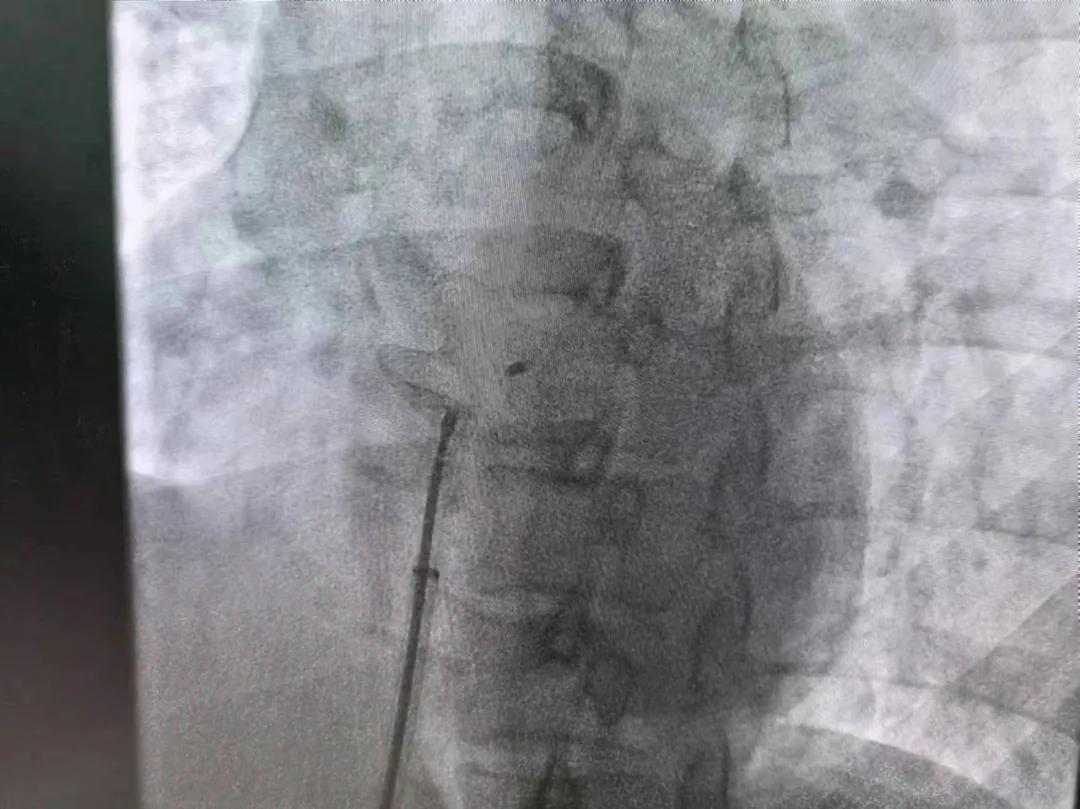

繼3月14日市二院成功開(kāi)展首例卵圓孔未閉介入封堵術(shù)之后,3月21日上午,市二院院長(zhǎng)王瑾及心血管內(nèi)科主任李慧新帶領(lǐng)心血管內(nèi)科介入團(tuán)隊(duì),再次成功為患者實(shí)施“經(jīng)皮房間隔缺損封堵術(shù)”,手術(shù)過(guò)程順利。該例病人的成功手術(shù)及康復(fù),標(biāo)志著市二院心血管內(nèi)科在結(jié)構(gòu)性心臟病介入診療中再次達(dá)到了新高度。

患者為中年女性,41歲,近2年一直反復(fù)出現(xiàn)頭暈、頭痛,曾先后在多家醫(yī)院就診。近期患者癥狀加重,出現(xiàn)活動(dòng)后氣喘合并胸悶癥狀,來(lái)到心血管內(nèi)科就診。經(jīng)心臟彩超檢查顯示:患者房間隔下段連續(xù)性中斷,缺損直徑達(dá)到了13mm,肺動(dòng)脈壓已經(jīng)輕度增高,確診為房間隔缺損。

于是,院長(zhǎng)王瑾會(huì)診后,詳細(xì)詢(xún)問(wèn)患者病史,認(rèn)真分析臨床癥候群并準(zhǔn)確診斷,耐心做好患者及家屬病情告知和充分溝通。經(jīng)過(guò)完善的術(shù)前評(píng)估及準(zhǔn)備,心血管內(nèi)科介入團(tuán)隊(duì)成功為患者實(shí)施“經(jīng)皮房間隔缺損封堵術(shù)”,手術(shù)過(guò)程順利。近日,患者已順利康復(fù)出院。 (尹紅婭 潘長(zhǎng)林)